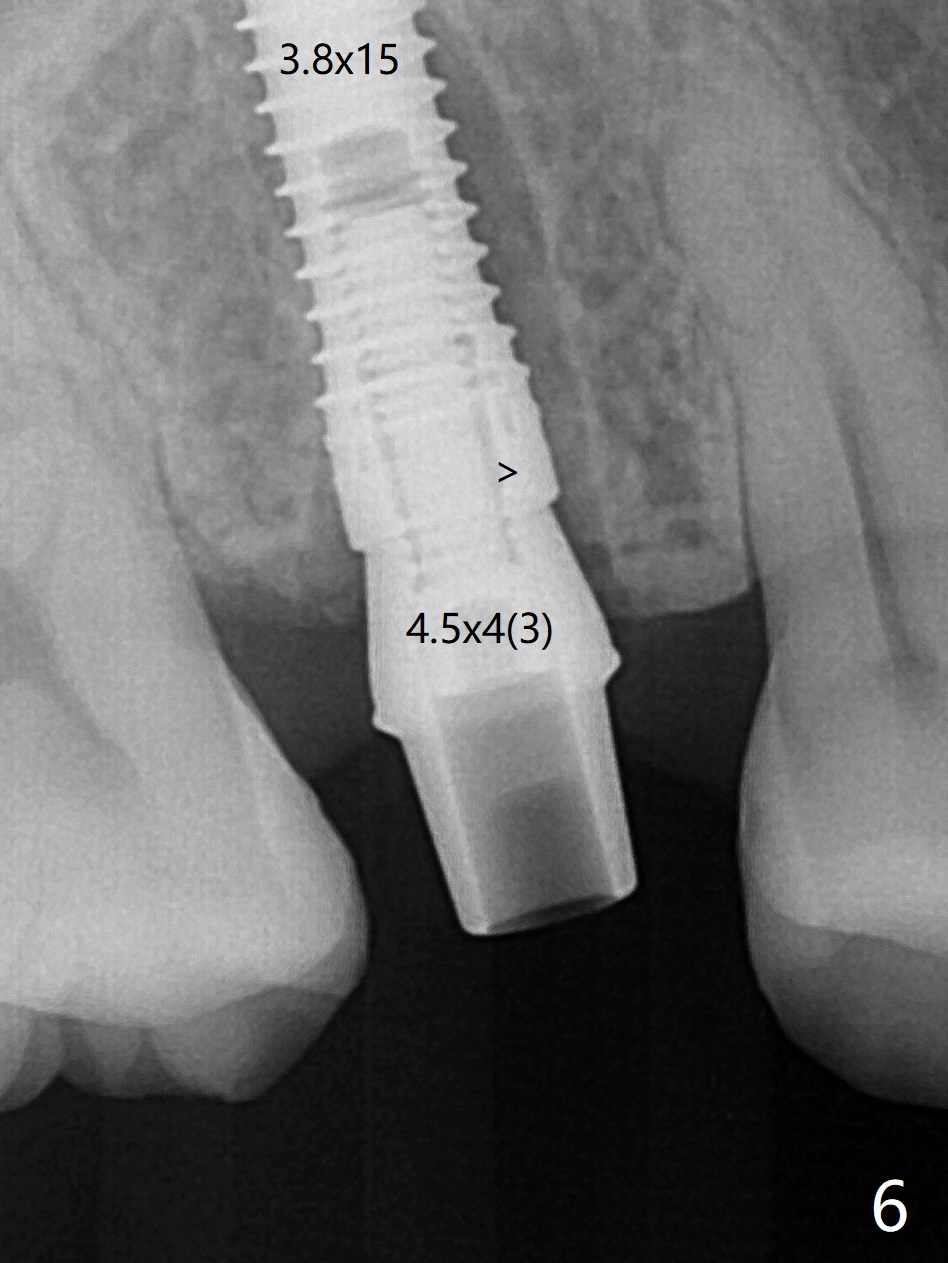

4号牙残根(图一)无创伤拔除使用一种叫做proximators牙周刀(periotomes,图二,三)。初期钻洞方位尚可(图四,五),植入3.8x15毫米植体,扭力50Ncm,修复成品基台完全就位(图六,七),植体,基台周围间隙填入骨粉(用血液调袢)后,制备基台(图八)和临时牙冠。